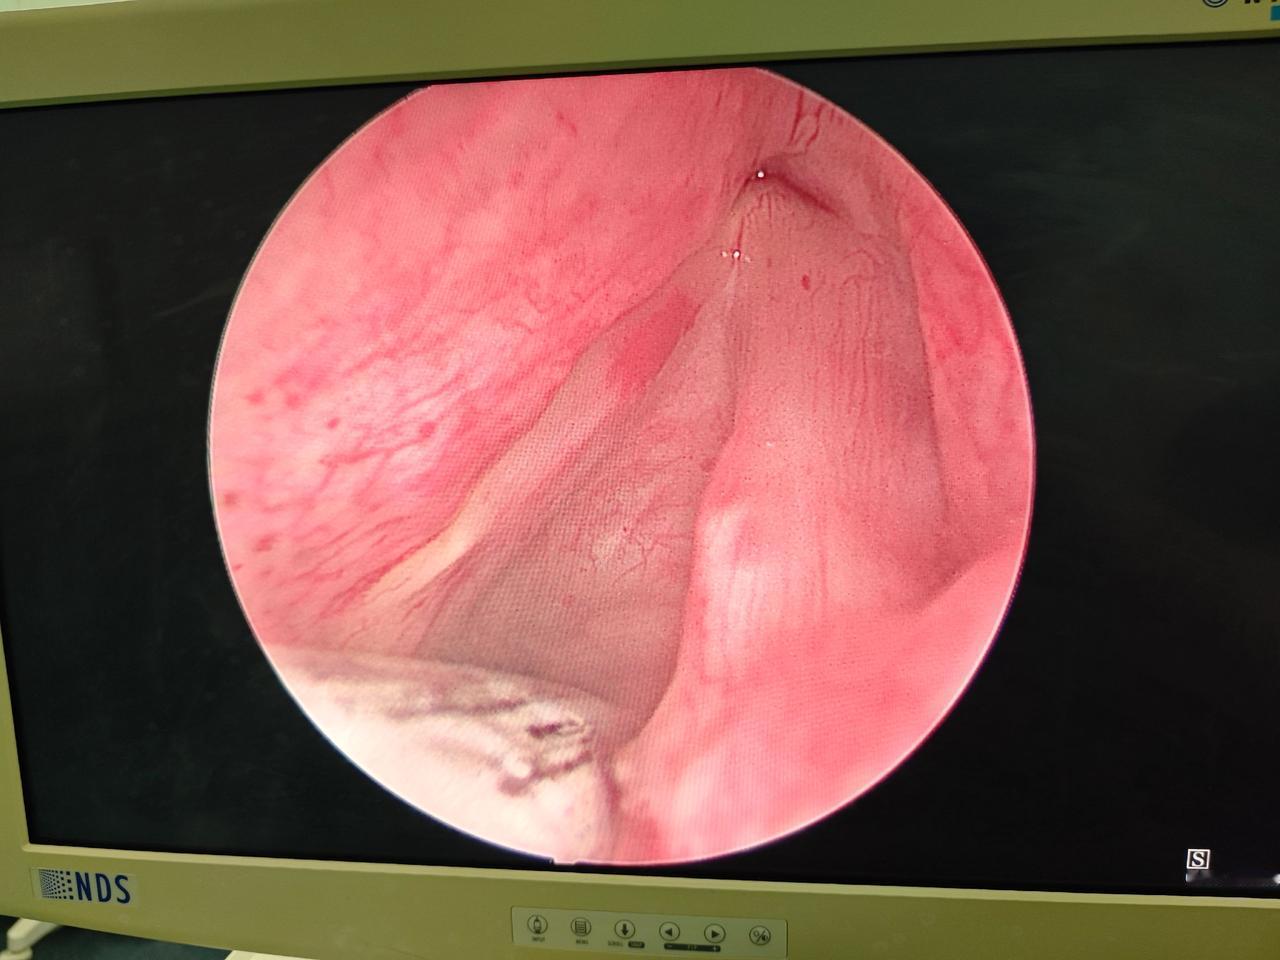

别再说声带息肉是小手术!只有耳鼻喉医生才懂这种几近崩溃的无助! 今天做完最后一台声带息肉手术,心里久久不能平静。患者是一位50岁男性,术前评估就不乐观:喉结偏高、舌体肥厚、咽腔狭窄,属于典型的困难气道。 上台后,果然和预判一样,常规支撑喉镜根本无法暴露声门,反复调整角度都看不到术区。那一刻,压力真的很大,既怕暴露不足做不干净,又怕用力过猛损伤咽喉黏膜、松动牙齿。 没有退路,只能想尽办法。结合之前经验,我果断更换前联合镜,搭配30°内镜,甚至把息肉钳手动掰成30°,一点点寻找最佳视野,精细分离、精准切除。全程高度集中,不敢有丝毫马虎。 万幸手术顺利完成,声带息肉完整切除,咽喉无拉伤、牙齿无松动,患者安全下台。 很多人觉得,声带息肉就是个小手术,几分钟的事。可只有我们耳鼻喉医生知道,每一台顺利的手术背后,都是无数细节在兜底。遇上困难气道,每一步都是考验。 既然穿上这身白大衣,就扛得起这份责任。不放弃,不马虎,不负每一位患者的信任。耳鼻喉医生,继续加油!